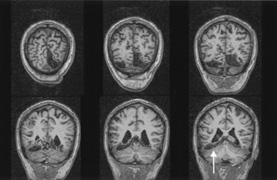

Fig. 10. Striate quadrantanopia. A. A 68-year-old woman with a stroke 3 years previously, causing left inferior quadrantanopia. B. MRI shows infarct of the superior bank of the right calcarine cortex.

The upper and lower banks can also be involved separately. Ischemia can do this because the banks have separate blood supplies. Upper bank infarcts cause homonymous contralateral inferior quadrantanopia (Fig. 10) and lower bank infarcts cause superior quadrantanopia. Although altitudinal defects have been reported occasionally,47,48 most quadrantic defects do not align at the horizontal meridian, because the upper field merges without interruption into the lower field in the depths of the calcarine fissure. Thus it has been argued that quadrantic defects that respect the horizontal meridian are caused by involvement of area V2, surrounding striate cortex,49 which remains controversial. Quadrantanopias are three times more common with striate lesions than with optic radiation lesions.33 Striate quadrantanopias are more frequently isolated signs but can be associated with other signs of higher cortical visual dysfunction, such as pure alexia or hemiachromatopsia, whereas optic radiation quadrantanopias usually are accompanied by hemiparesis, dysphasia, or amnestic problems.33